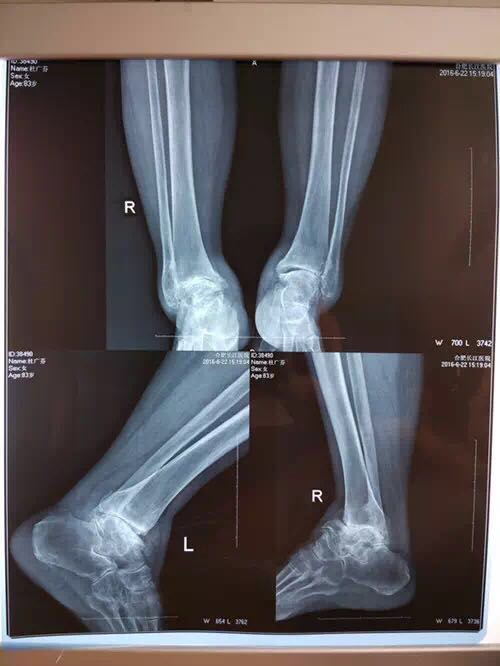

下图为杜老太在医院拍的X光片

经过触诊,她的双侧踝关节外翻、变形;肌肉、肌腱痉挛,变形部位大面积增生。